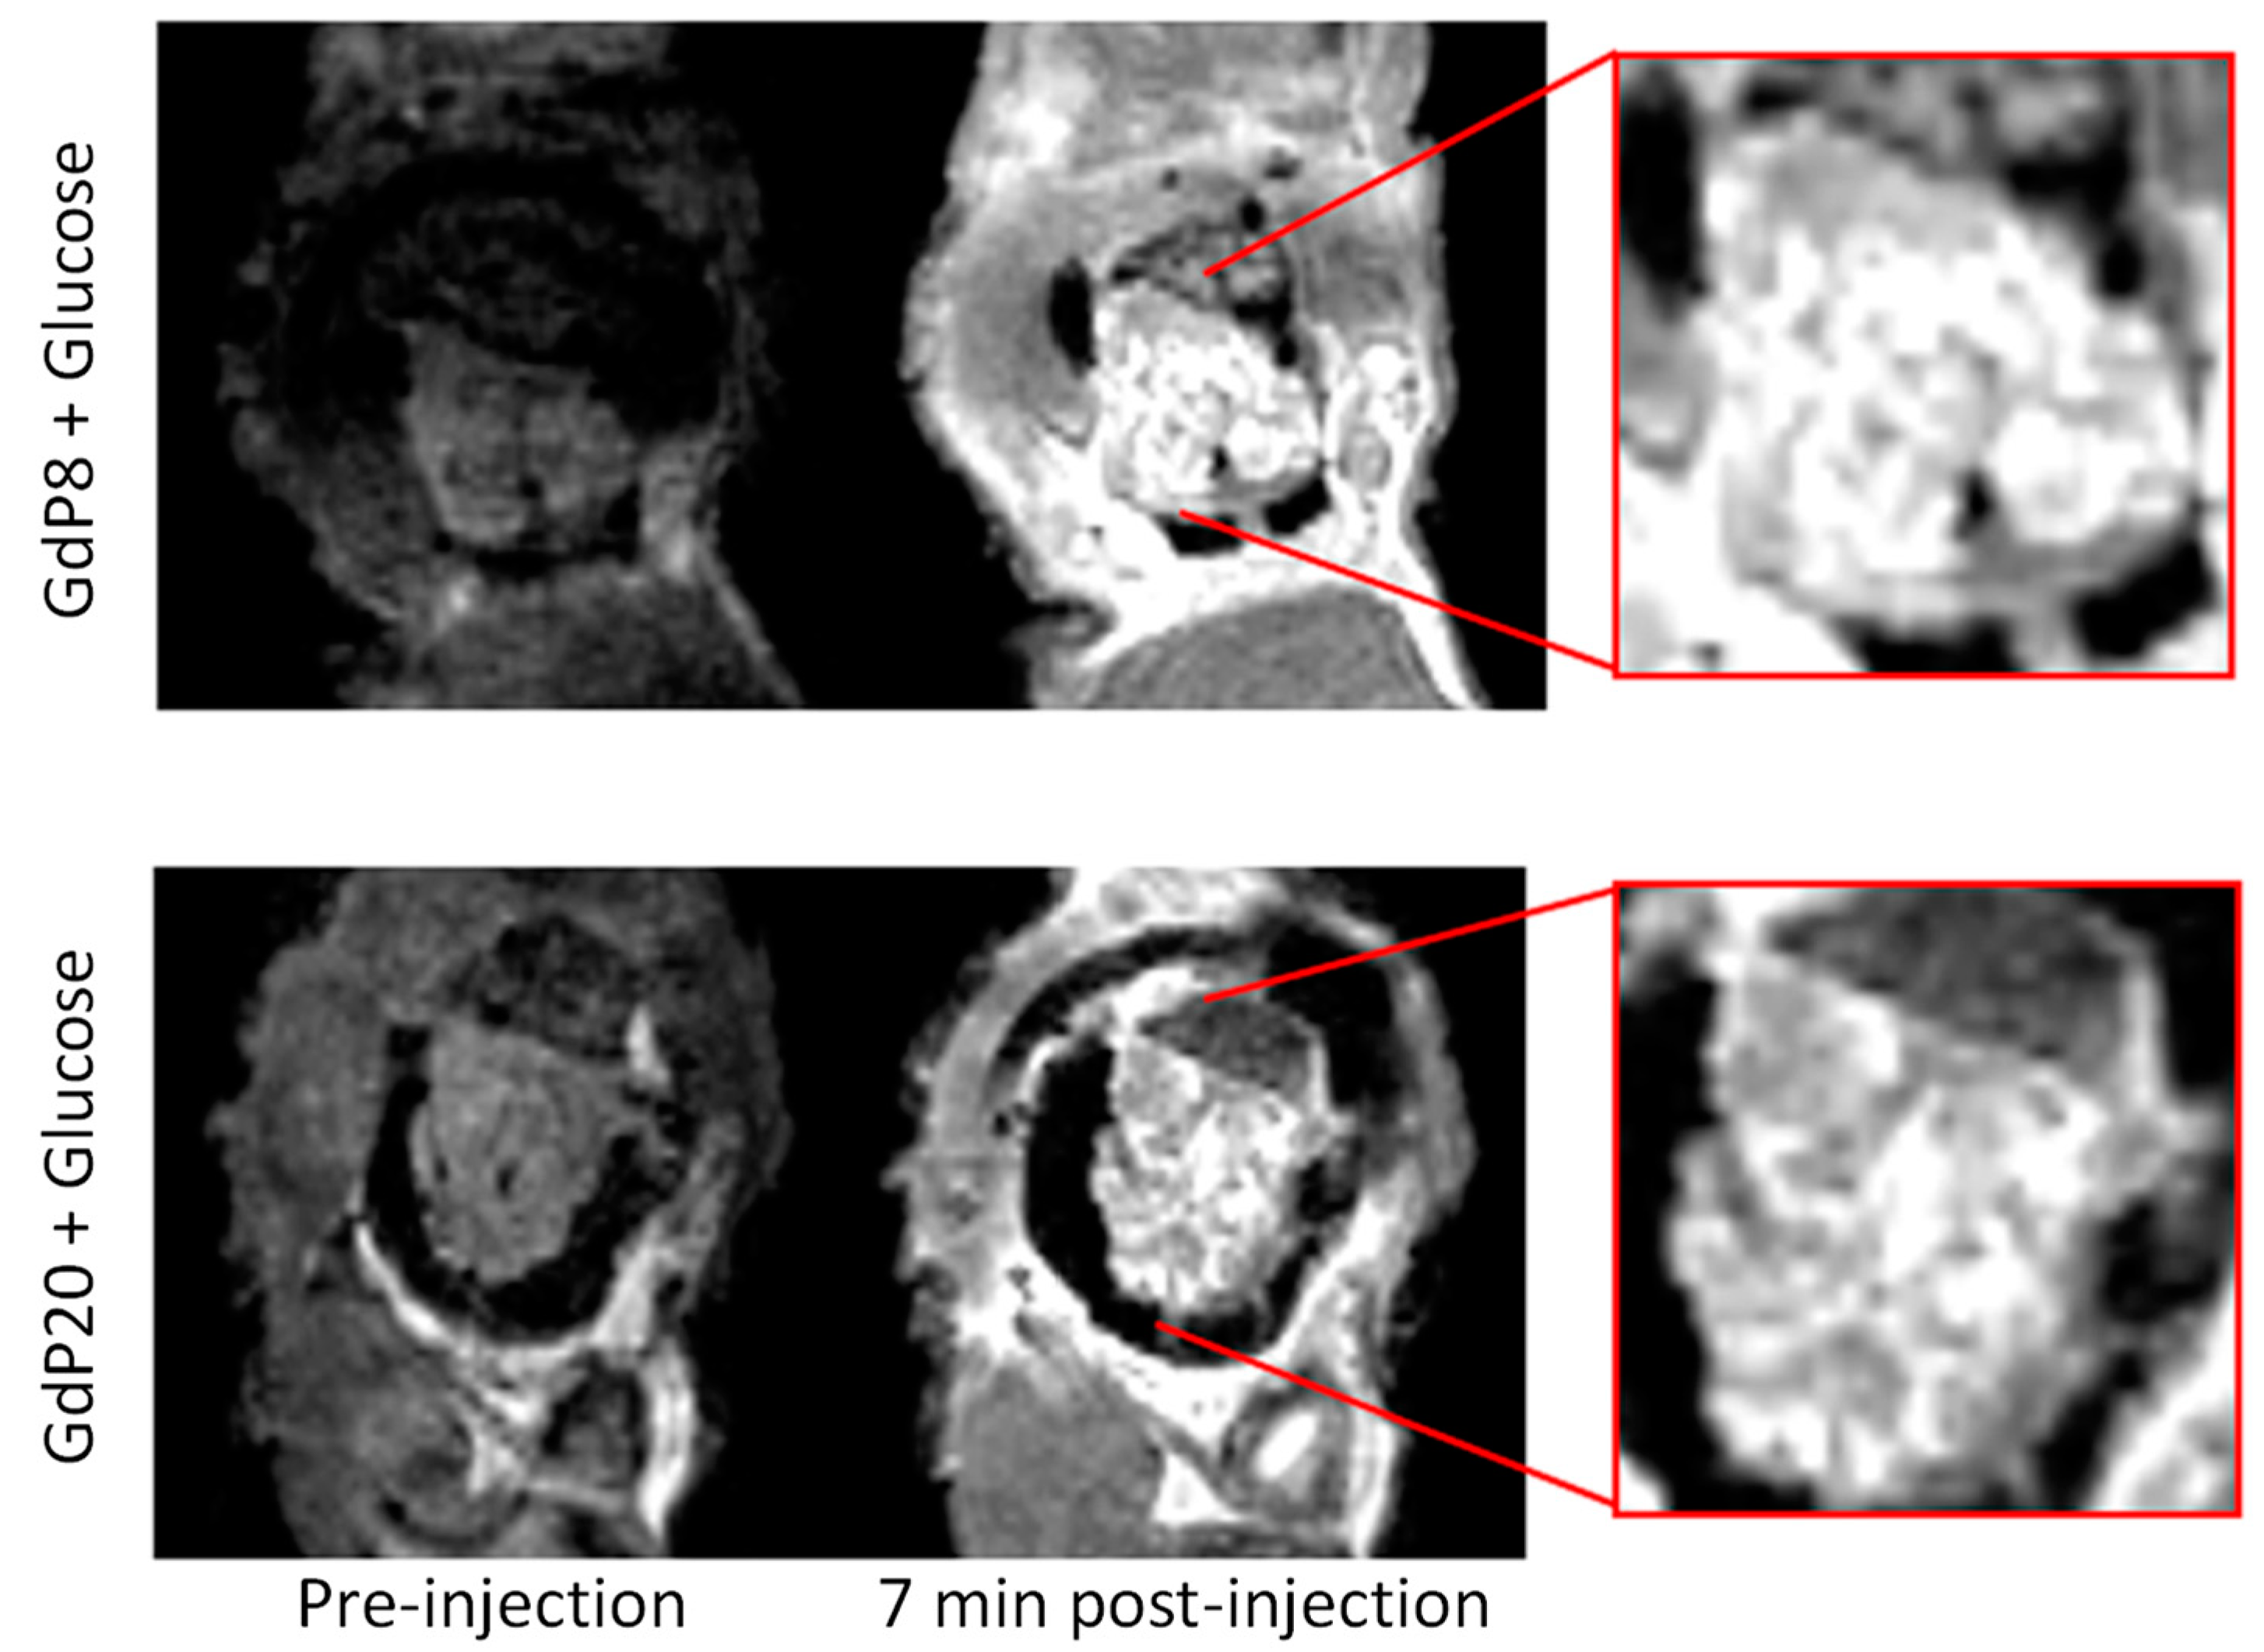

| GdP8 | Zn | 118 nM | 200 | Interaction with HSA | No | Ca, Mg | [58] | |

![]() | GdP20 | Zn | 2350 nM | 100 | Interaction with HSA | nd | nd | [58] |